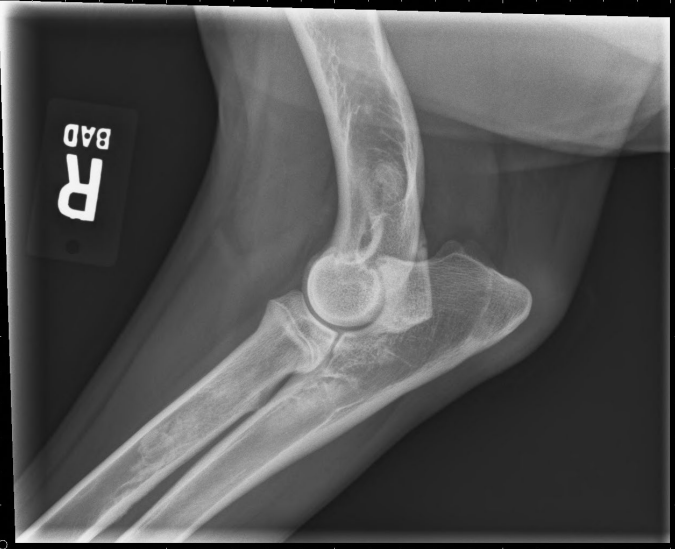

사진 모음

- arrow : 두꺼워진 골막

- arrowhead : 뿌옇게 보이는 골수관

- 범골염 증상 (비교적 명확)

- 범골염 증상

- 범골염

- trabecular pattern

- 겉질과 골수관의 대비가 감소. 구별이 잘 되지 않아 경계가 흐릿